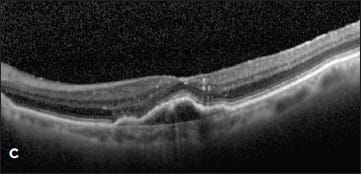

Figure 3. A patient with a new serous PED and CNV identified by ICG was treated with ranibizumab, followed by monthly aflibercept (A and B). Despite treatment, the PED worsened with increasing size and SRF (C). The patient then underwent PDT to the area of the choroidal feeder vessel without resolution (D).

Case 4. Such was the case of a 56-year-old woman who presented with a large serous PED with small amount of subretinal fluid (Figure 4A). Her vision had dropped from 20/20 to 20/400. Fluorescein angiography revealed a notch at the inferior-temporal border of the PED. ICG angiography showed a large, dilated vessel at 7 o’clock (Figure 4B).

The patient was treated with intravitreal aflibercept without improvement and then was switched to intravitreal ranibizumab. Despite treatment, the PED grew in size, and the subretinal fluid increased (Figure 4C). She was re-evaluated with ICG angiography (Figure 4D), and then was treated with PDT to the area of the choroidal vessel identified at 7 o’clock.

Four months later, the PED was unchanged, and she was retreated with PDT in combination with her monthly aflibercept. One month after the second PDT, her vision and exam remained unchanged.